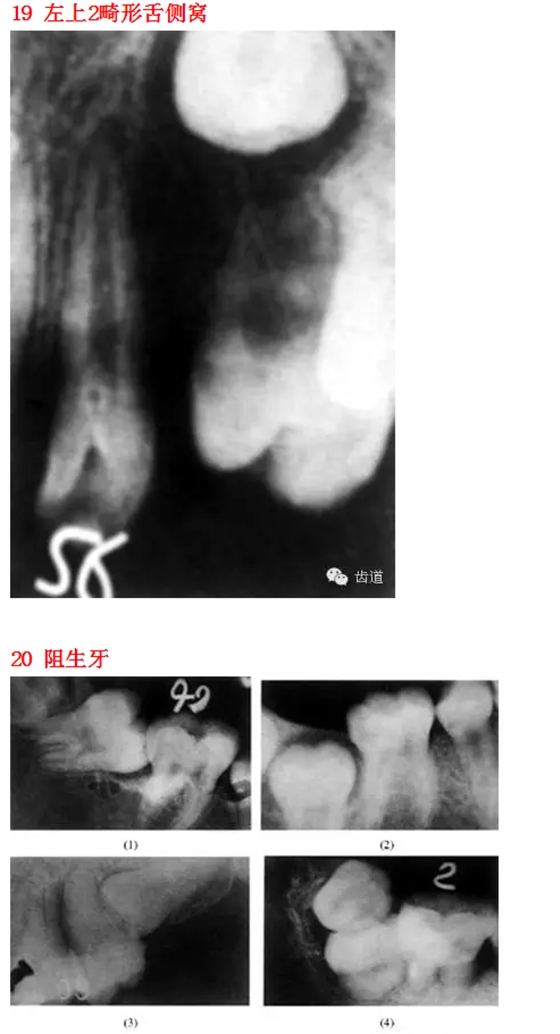

首頁(yè)口腔影像 26種口腔病變X光片

26種口腔病變X光片